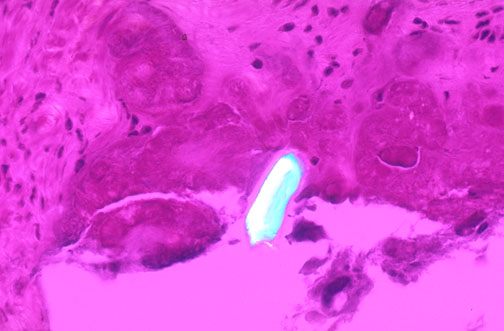

A rhromboid shaped crystal of calcium pyrophosphate dihydrate (CPPD) appears bluish-white (weak positive birefringence) by polarized light microscopy with a red plate. Calcium pyrophosphate crystal deposition disease (sometimes called "pseudogout") is most often seen in persons over the age of 50, and can lead to acute, subacute, or chronic arthritis of knees, wrists, elbows, shoulders, and ankles. The articular damage is progressive, though in most persons the disease is not severe. |